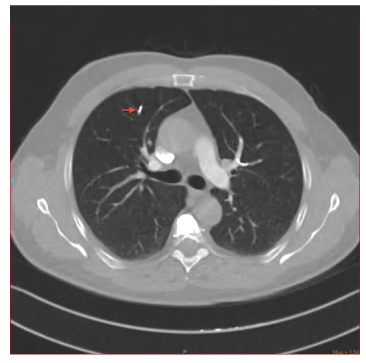

48岁男性,有慢性阻塞性肺疾病病史,诊断为复发性葡萄膜炎,但没有结节病或结核病的证据。他接受了脉冲类固醇和口服类固醇作为维持治疗葡萄膜炎。他还有30年的吸烟史。骨质疏松症继发自发性椎体压缩性骨折。每11个椎体均行经皮椎体成形术。术后第一天患者突然出现呼吸急促、胸痛和心动过速。血压正常,心率116 /min。肺听诊叩诊清晰,心脏及其他查体正常。血液化学分析及pH: 7.46, pCO无明显变化2: 38mmhg, pO2: 58mmhg, HCO3.: 28, SaO2: 91动脉血气分析。胸部计算机断层CT血管造影显示右上、下叶半奇静脉内因辐射不透明而出现致密物质(图1-3)。行超声心动图及下肢多普勒超声检查,未见病理改变。这些结果与水泥PMMA肺栓塞、低分子肝素低分子肝素抗凝和氧疗相一致。一周后,低氧血症得到缓解,患者接受低分子肝素治疗出院回家。对照组CT血管造影显示6个月时PMMA栓塞无变化,并行通气灌注闪烁(VQ)检查。VQ扫描也显示右上叶前部和左上叶尖后低灌注失配区,但患者治疗后无症状(图4、5)。

图3:入院时胸部CT检查

图4:低分子肝素治疗后胸部CT检查